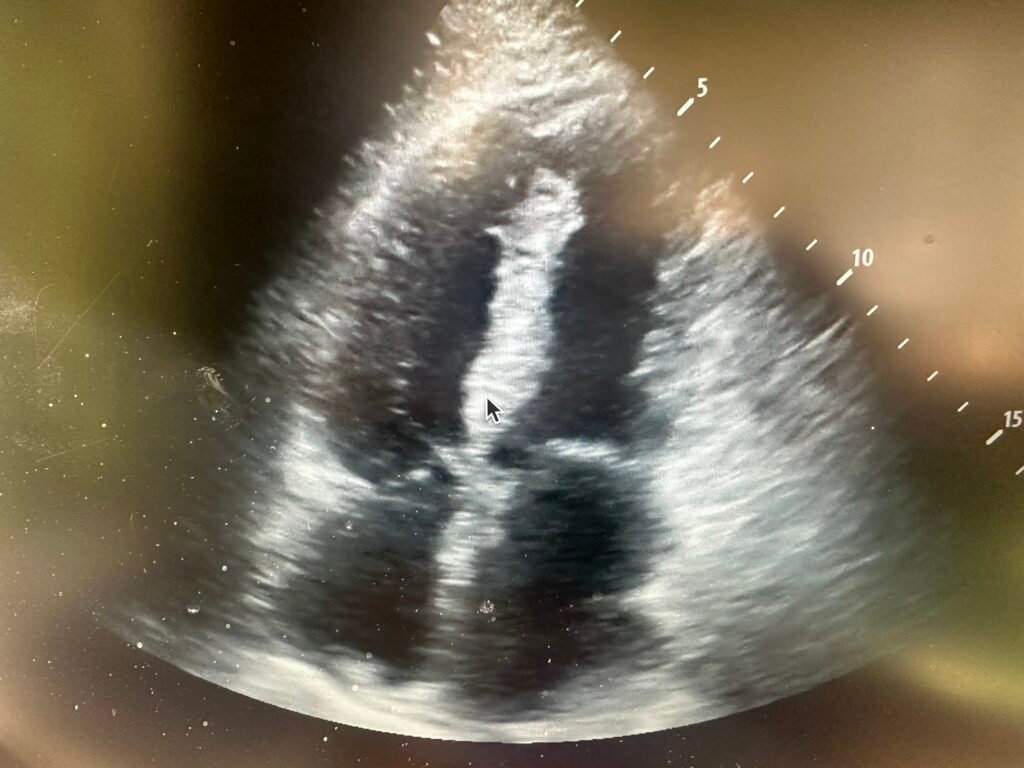

A bedside echo was recorded as part of the workup for hypotension:

Above is the video taken at the start of the case. Here is a still image from that video. What do you see?

There is a large ventricular septal rupture. I could hardly believe my eyes because the patient was comfortable without dyspnea or chest pain, and after fluids had a normal blood pressure.

Because of this, I was not at all certain that I was interpreting the ultrasound correctly.